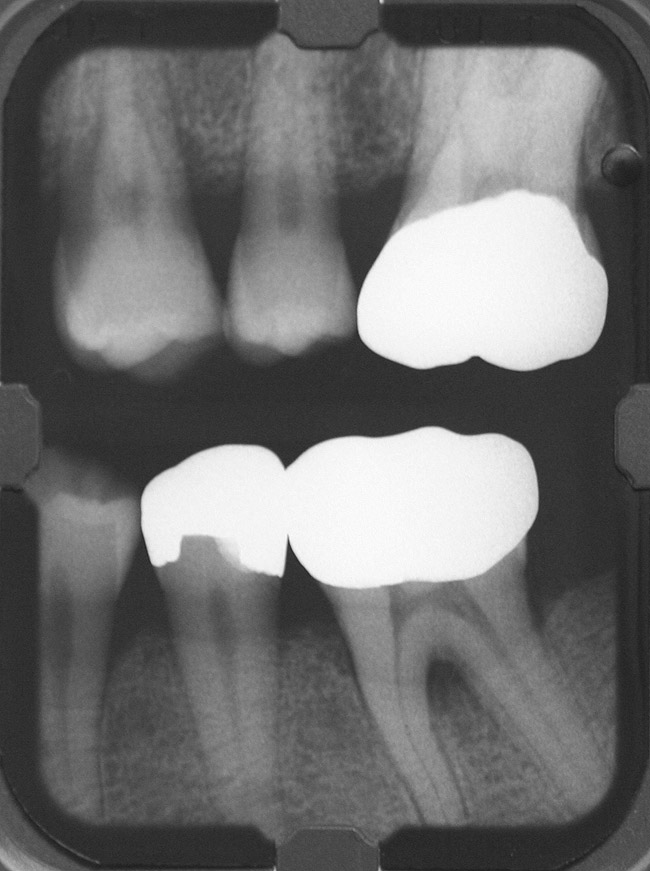

Inflammation limited to soft tissues around a dental implant may result from dental plaque colonization and is termed peri-implant mucositis. This is a reversible inflammatory condition limited to the soft tissues around the implant (without any bone loss), analogous to gingivitis around natural teeth. A diagnosis of peri-implantitis results when the inflammation spreads apically, causing progressive loss of osseointegrated supporting bone, analogous to periodontitis around natural teeth16 (Figure 2A and Figure 2B). It is essential for practitioners to be familiar with these diagnostic terms when assessing the long-term success of implants and peri-implant health (Table 1).

Figure 2a

Figureb 2  (A) Clinical and (B) radiographic views of implants at site Nos. 30 and 31 demonstrating bone loss caused by peri-implantitis after 8 years in function. Note gingival inflammation and plaque accumulation around implants.

Figure 2b